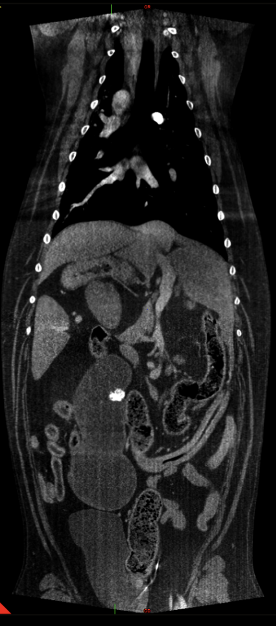

Abdomen: Ein wesentlicher Schwerpunkt unserer klinischen Arbeit liegt im Abdomen. Neben der Darstellung abdominaler Tumoren und struktureller Organveränderungen konnten auch Gefäßanomalien wie portosystemische Shunts erfolgreich dargestellt werden. Für viele klar definierte Fragestellungen stellt das CBCT eine praktikable und diagnostisch wertvolle Alternative zum MSCT dar (Abb. 5 & 6).